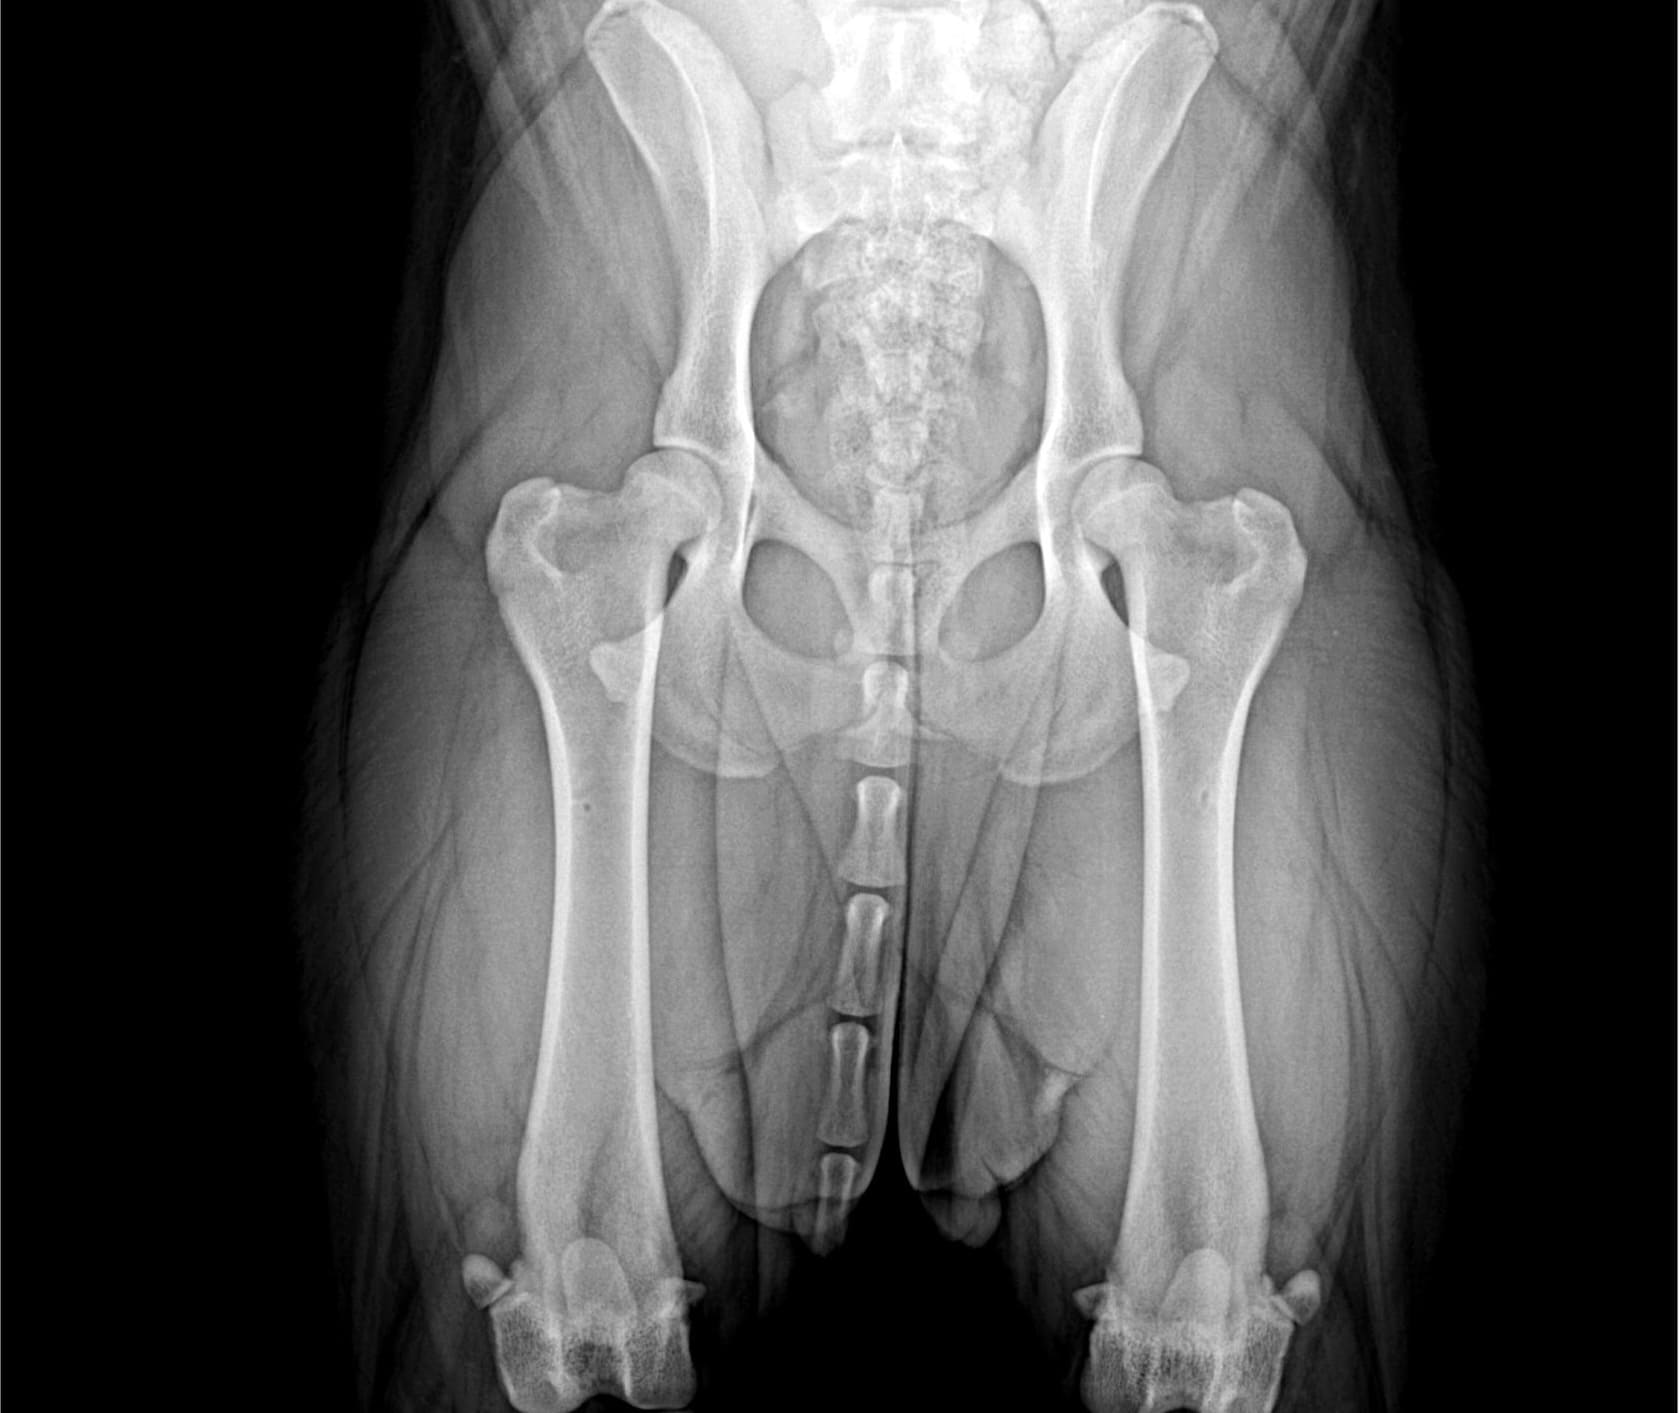

El diagnóstico de la displasia de cadera en perros grandes suele incluir:

Radiografías